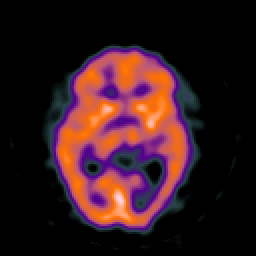

SPECT TC Study #8 -- Slice #26

[Home][Help][Clinical][Tour 1][Tour 2][Tour 3] Slice 26